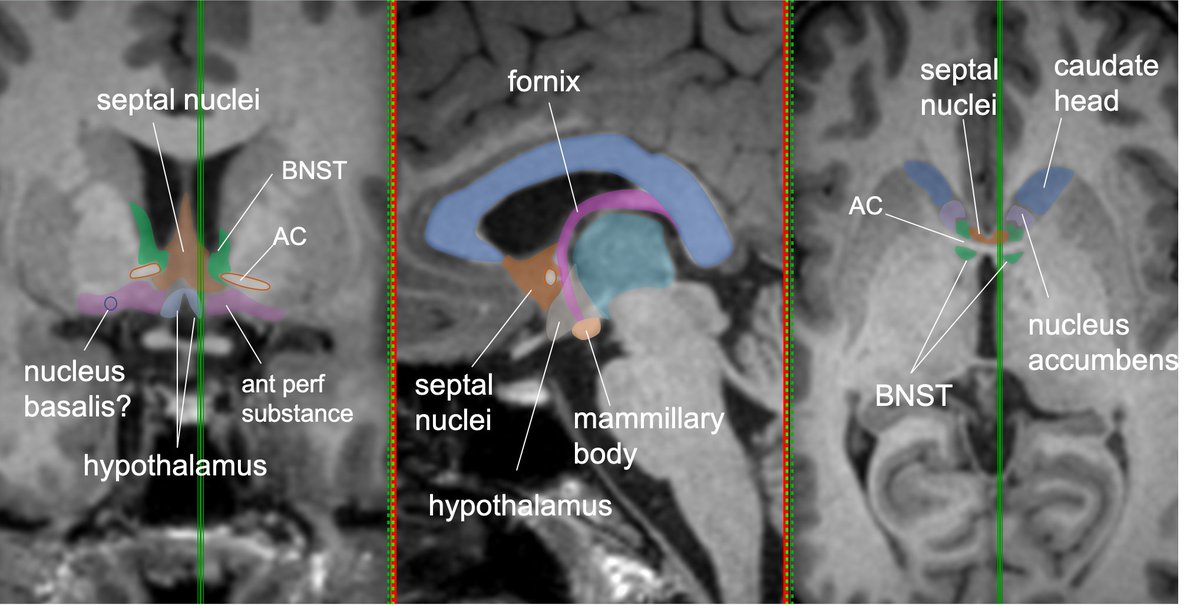

Coursing anterior, the ST appears to enlarge just post to ant commissure—this is the bed nucleus of the stria terminalis (BNST), a functional extension of the amygdala-an integration hub for limbic functions & valence-important in stress response,fear states,social behavior

This BNST hub has connections with 3 main pathways: supracommissural, commissural, and subcommisural.

Supracommisural passes above and in front of AC, terminates in septal nuclei and nucleus accumbens (pleasure and reward circuit).

Commissural pathway joins AC➡️communications between hemispheres and bilateral amygdalae.

Subcommisural pathway➡️hypothalamus--important connections to hypothalamic-pituitary-adrenal axis (important in emotional/fear response).

Note: lots of confusion about structures of basal forebrain ant/inf/about the AC—for good reason! Mixed GM/WM of ant perforated substance, substantia innominata/nuc Basalis, septal nuclei/BNST, nuc accumbens, subcallosal cortex-all in close proximity, similar MR intensity